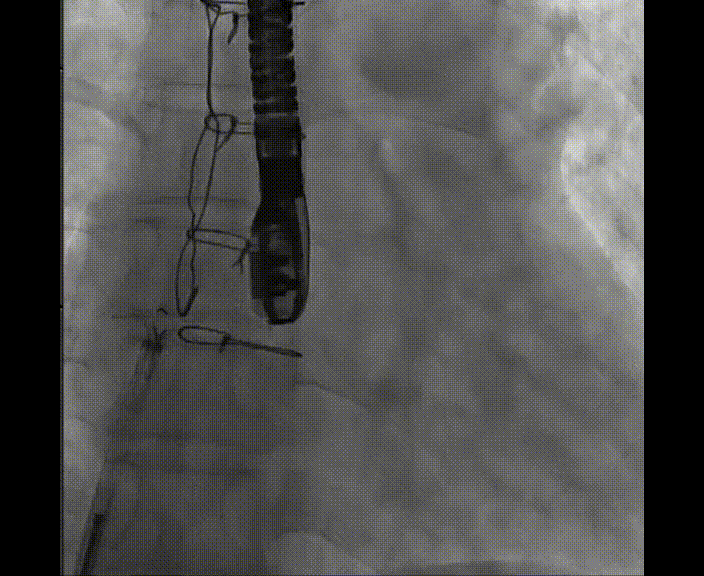

術(shù)中首先在局麻下穿刺股動脈、股靜脈,完成心導(dǎo)管檢查評估后轉(zhuǎn)為全麻,在食道超聲引導(dǎo)下穿刺房間隔,穿刺成功后將加硬導(dǎo)絲送入左上肺靜脈建立軌道,根據(jù)患者病情行球囊預(yù)擴張后植入6mm孔徑房間隔造孔支架,經(jīng)透視及食道超聲評估支架左右盤展開良好,夾持于房間隔兩側(cè),固定穩(wěn)定、位置良好,食道彩超顯示房水平右向左為主分流,分流孔直徑符合預(yù)期大小,心導(dǎo)管檢查評估達到預(yù)期效果,釋放造孔支架。術(shù)后12h患者下床活動,恢復(fù)順利,擬于近日完善術(shù)后評估后出院。